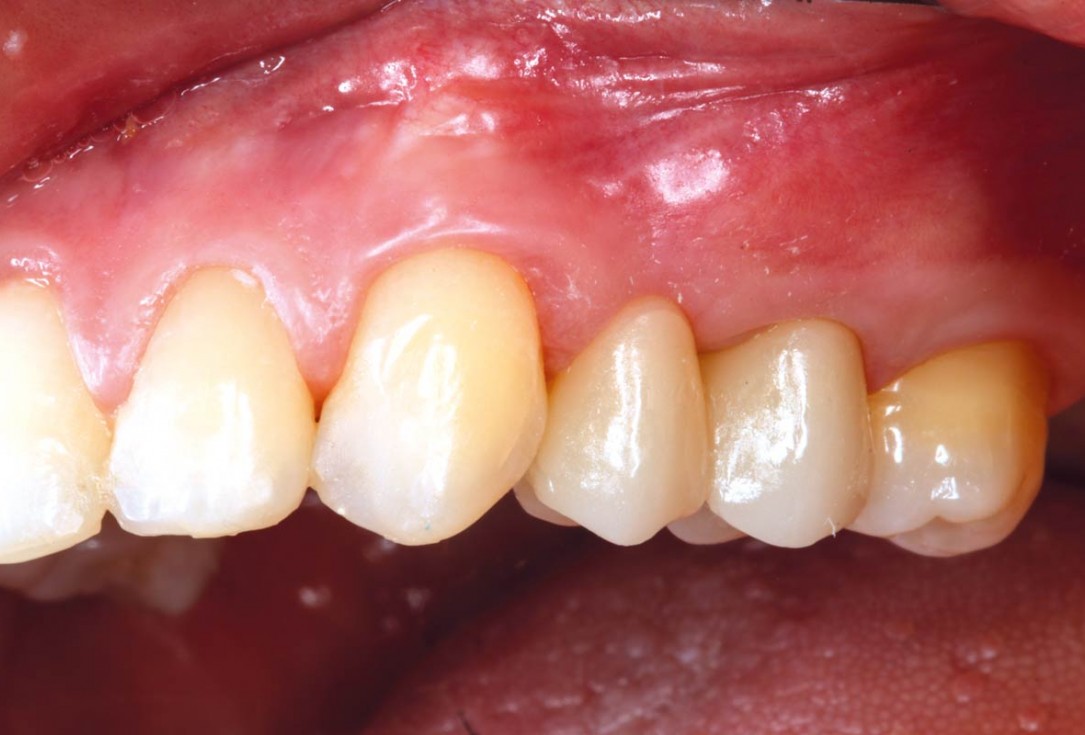

11/11 - After prosthodontic treatmentRidge reconstruction with maxgraft® block in the posterior maxilla - Dr. A. Puišys